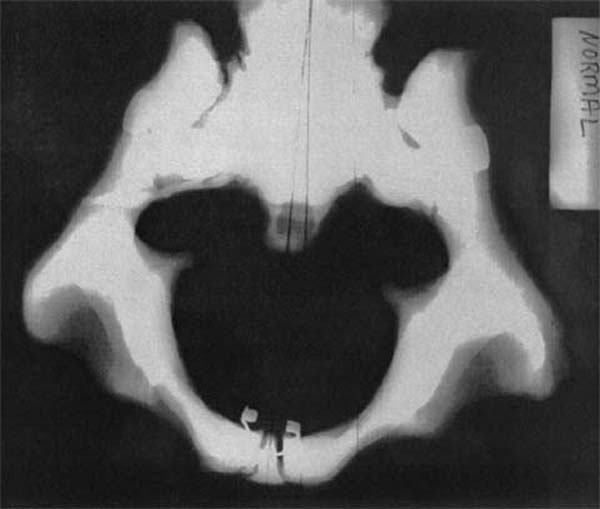

When the sacrum is in a neutral position relative to the right and left innominates, the pelvic bowl has a uniform, symmetrical opening (Figure 1).

Figure 1 is a superior to inferior (S to I) radiographic view of a model demonstrating normal pelvic perimetry. Notice the symmetry and relative roundness of the pelvic bowl with respect to the midline. A model was used for the radiography because of the inherent risk associated with the use of radiography during pregnancy. Moreover, radiographs of nonpregnant patients were not used because it is believed that they would not exhibit the 1– to 3–mm multidirectional movement in the sacroiliac joints that occurs in pregnancy and parturition as described by Schafer. [70]

| Figure 1.

Normal unsubluxated female pelvic bowl.

(Model) S to I view. Note symmetry

and relative roundness of opening.

(Radiograph provided courtesy of

Cherie Goble, DC.)